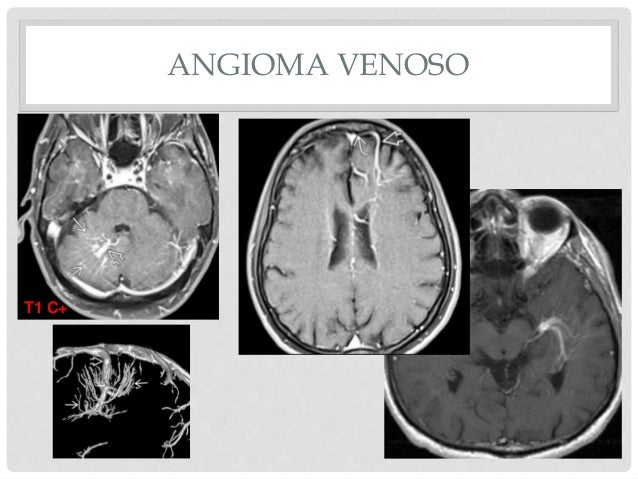

Cerebral venous angioma (developmental venous anomaly) is the most common cerebral vascular malformation It consists of an intraparenchymal tangle/cluster of dilated medullary veins converging on a single enlarged draining vein It rarely bleeds. L’angioma cerebrale è una patologia che può rivelarsi molto grave e in qualche caso anche fatale ma che nella maggioranza dei casi è congenita e decorre in maniera asintomatica La terapia dell’angioma cerebrale è molto complessa e normalmente se l’angioma non è posizionato in distretti anatomici con importanti funzionalità si preferisce non trattarlo ma monitoralo semplicemente. Devemos ressaltar que até aproximadamente 40% dos casos diagnosticados de angiomas cerebrais se desenvolvem esporadicamente paralelamente a outra anomalia vascular, especificamente o angioma venoso (Angioma Alliance, 16).

Abstract Seven patients with angiographically proved cerebral venous angiomas were imaged by magnetic resonance The venous angioma was identified in all cases The most characteristic feature was an enlarged transcerebral draining vein (86%), followed by increased signal on T2weighted images (57%) and decreased signal on T1weighted images (40%) in adjacent parenchyma. Introducción La incidencia del angioma venoso (AV) es de 2,53,5% en la población general y representa el 60% de las malformaciones vasculares cerebrales (MVC) conocidas, que incluyen telangiectasias capilares, cavernomas y malformaciones arteriovenosas que aportan con el %, 10% y 9% de frecuencia, respectivamente 1Los términos AV y anomalía del desarrollo venoso (ADV) se usan como. In altri casi, la chirurgia è la base del trattamento dell'angioma venoso del cervello Per oggi in un arsenale di medici ci sono alcuni metodi di asportazione di un tumore Alcuni metodi prevedono un trattamento passopasso e alcuni eseguono una rimozione completa entro un intervento chirurgico.

Developmental venous anomaly (DVA), also known as cerebral venous angioma, is a congenital malformation of veins which drain normal brain They were thought to be rare before crosssectional imaging but are now recognized as being the most common cerebral vascular malformation, accounting for ~55% of all such lesions. El tratamiento láser se dirige al capilar venoso seleccionado para que se aumente la temperatura de la sangre, que en milésimas de segundo se coagula y provoca que el tumor se desvanezca Esta técnica corrige la lesión vascular y no afecta a tejidos y estructuras cercanos, por lo cual es recomendada incluso en niños. Las anomalías venosas del desarrollo (AVD), también conocidas como angiomas venosos, son variantes anatómicas congénitas en el trayecto del drenaje venoso en una zona determinada del cerebro Son la malformación vascular cerebral más frecuente (Zimmer A et al 07).

Developmental venous anomaly (DVA), also known as cerebral venous angioma, is a congenital malformation of veins which drain normal brain They were thought to be rare before crosssectional imaging but are now recognized as being the most common cerebral vascular malformation, accounting for ~55% of all such lesions. De una paciente puérpera adolescente, con trombosis venosa cerebral que además tuvo un angioma venoso cerebral interauricular, que a los 21 días del puerperio presenta cefalea de moderada intensidad en región occipital y posteriormente hemiparesia derecha, con recuperación del defecto en 42 h. El hemangioma cerebral es por lo general una malformación congénita en forma de neoplasia Sus causas son en la actualidad poco conocidas Sus causas son en la actualidad poco conocidas Sin embargo, se ha detectado que existen variaciones como el angioma cavernoso familiar en la que se ha asociado el problema a mutaciones genéticas en el.